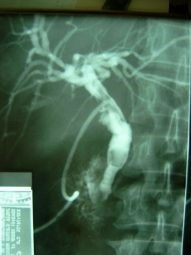

Extracción percutánea de cálculo de coledoco

Envíado por Dr. Carlos Miguel Zavaleta Consuegra